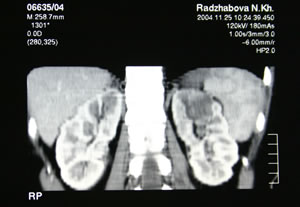

КОМПЬЮТЕРНАЯ

ТОМОГРАФИЯ: |

|